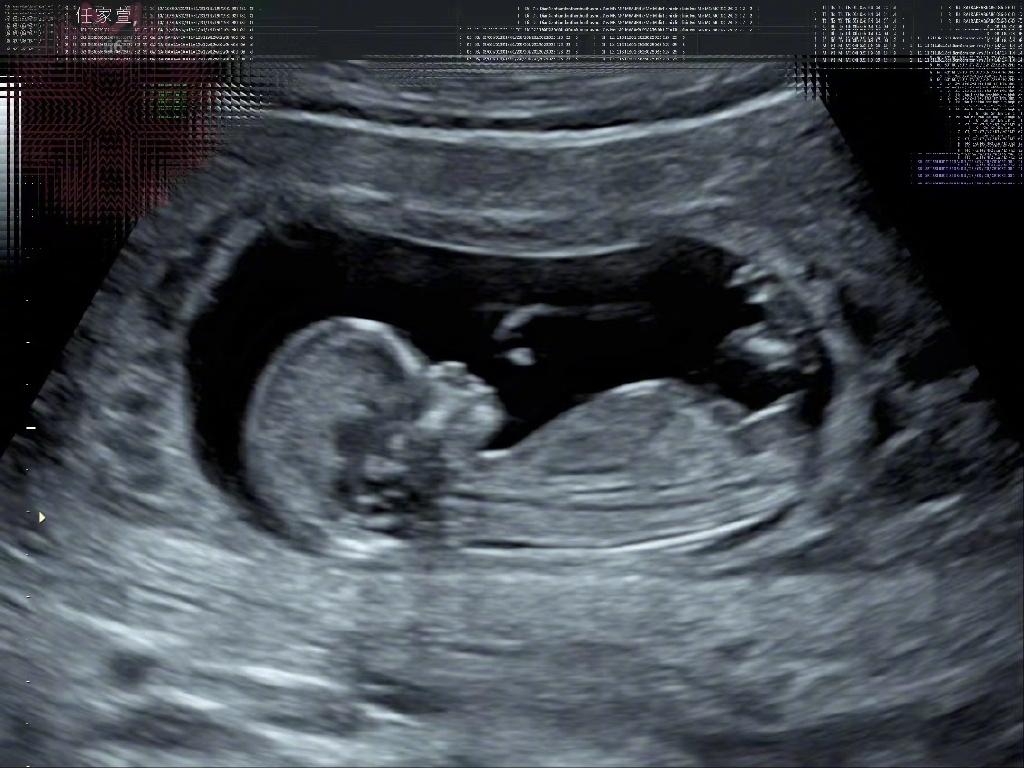

任家萱不结婚官宣怀孕!孩子名字已经取好! 任家萱是很多人心目中的女神,她在娱乐圈可以说是一位人美演技好的好明星,可是因为一场火灾让任家萱失去了爱情也失去了对自己的信任。经过这么多年的努力她如今也开始正常生活了,令人开心的是她还勇敢接受了新男友的求婚。不过两人并没有结婚,大家也没有过多打扰他们的生活。 3月13日任家萱突然官宣自己怀孕了,大家确实有点意外,任家萱也在自己的社交平台开心发文说:跟大家分享一个好消息,我~怀~孕~了!肚子里的宝贝,我取名叫“小腰果”! 原来任家萱真的怀孕了,大家给她送上祝福的同时也感叹她没有结婚就直接生孩子有点很突然,不过任家萱也经过很多不好的事情,所以她举办婚礼也是情有可原。